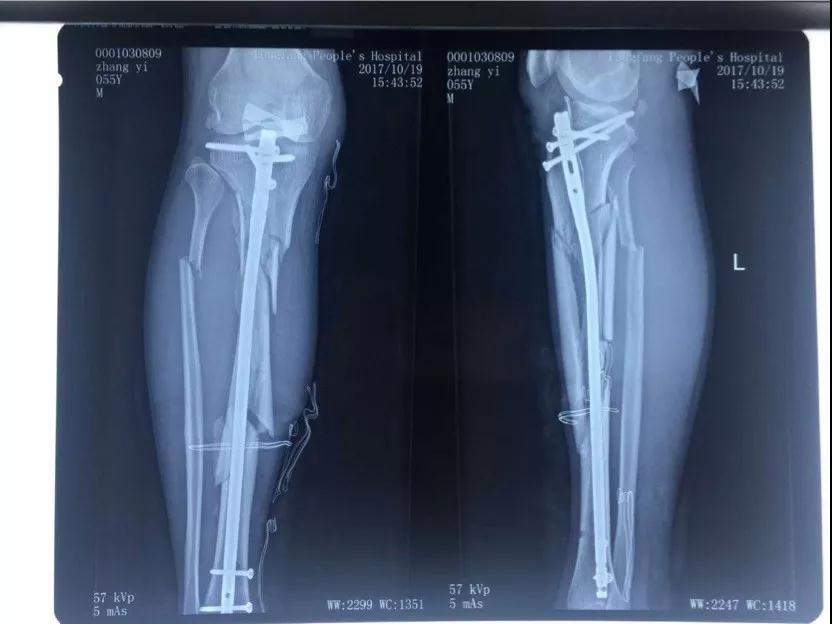

2017年10月18日十九大召開的當天下午五點多鐘,我像往常一樣去師範學院院裏老人居住的地方吃晚飯,此時,早已等待在老人樓下的一輛無牌照車裏出來四個蒙面人將我的腿打斷後逃走,這是十九大召開的的當日,是光天化日之下在大學的校園裏,是當着校園裏的教職工的面有預謀有組織的謀害。住院手術之後該團伙依然繼續到新院區繼續騷擾威脅,楊XX指使醫院會計在未履行任何財務手續的情況下從城南醫院挪用現金一千一百萬元,從兒媳婦XX也屬於城南醫院個人卡河北農信尾號XXXX中轉走五百萬元,此情況已經向安次區刑警隊和廊坊市公安局趙進晉局長報案’,至今至我傷殘和挪用醫院資金幕後指使依然逍遙法外。

2017年10月18日,張院長在廊坊師範學院院內遭受4名歹徒毆打至右腿粉碎性骨折,4名歹徒和背後指使者趙XX 均已落案。